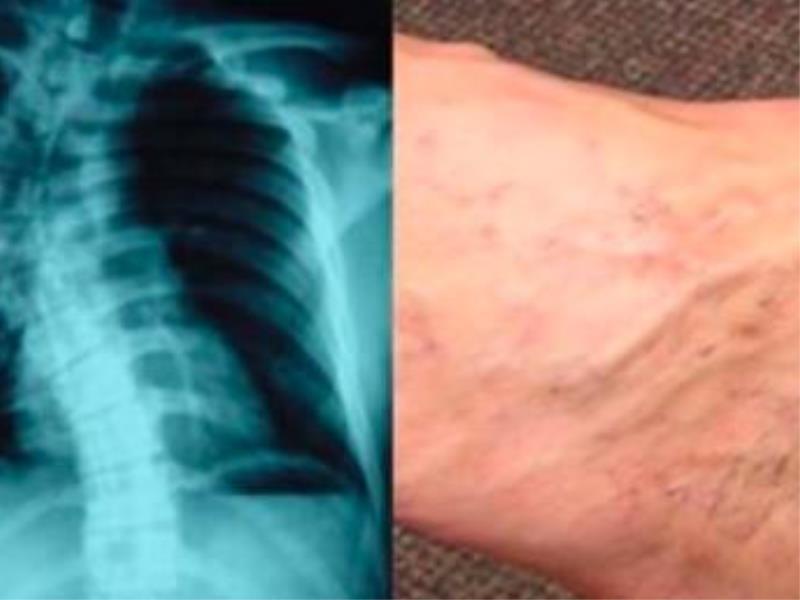

2、導致脊椎出現變形 正常的脊椎直的,從側面上是呈現S形狀的,那麼長期翹二郎腿會讓脊椎形成C字形,脊椎嚴重受到壓迫,在受力不均勻的情況下,就會出現變形的現象,嚴重的話還會出現腰椎間盤突出症。  蹺二郎腿雖然不會馬上讓你的身體出現一些疾病,但是長期這樣下去,到老年時期,很多症狀就會出現,例如骨關節炎,靜脈曲張等。  3、引發大腦和心臟供血不足 長時間處於腿部出現蹺二郎腿的狀態,會讓血液不能夠上下順暢的流通,血液循環過慢就會引發大腦和心臟供血不足,就會讓身體容易出現高血壓、 心臟病等現象。 4、蹺「二郎腿」致腰痛 專家介紹,腰痛是久坐的上班族女性中最常見的一種疾病。由於她們上班時喜歡蹺蹺「二郎腿」,極易造成腰椎與胸椎壓力分佈不均,引起脊柱變形晉劇戲曲,有的則會導致腰椎間盤突出,形成慢性腰背痛。  有專家認為,經常蹺二郎腿,還是加重頸椎病、 腰肌勞損的重要原因之一。